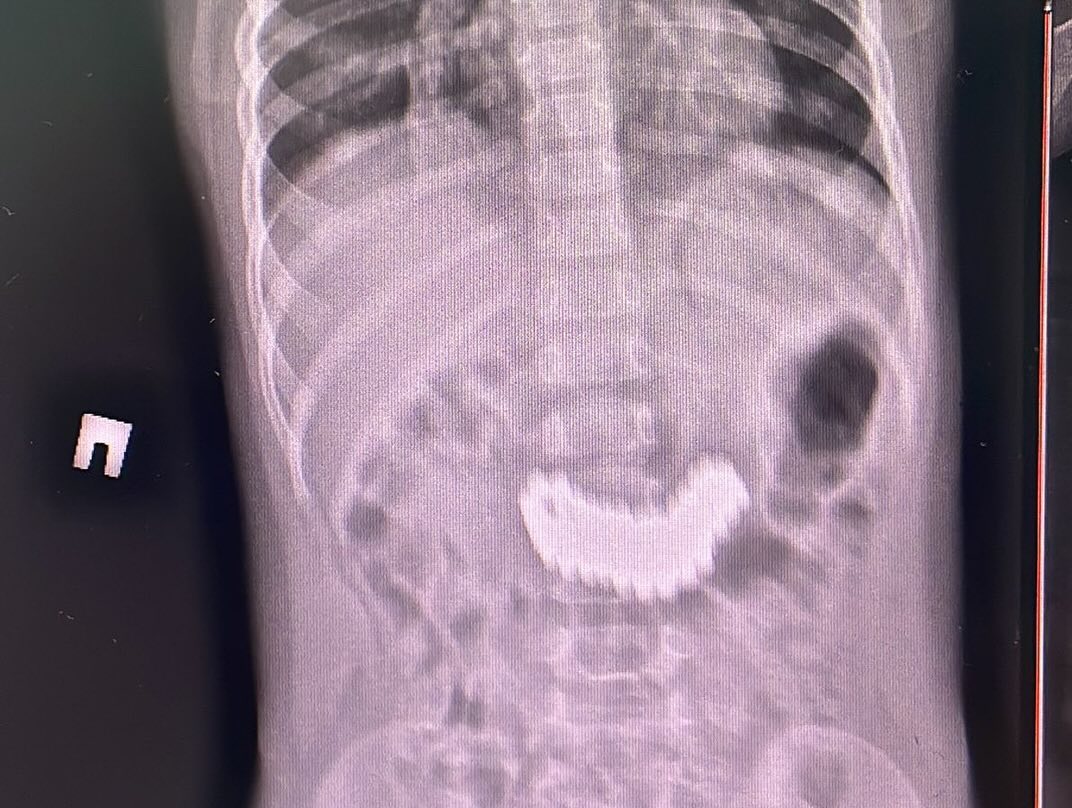

Как отметили в ЦДНМП, при проведении рентгенографии органов брюшной полости были выявлены металлические предметы размером 6,2 × 2,2 см. Ребенка экстренно госпитализировали для удаления инородного тела.